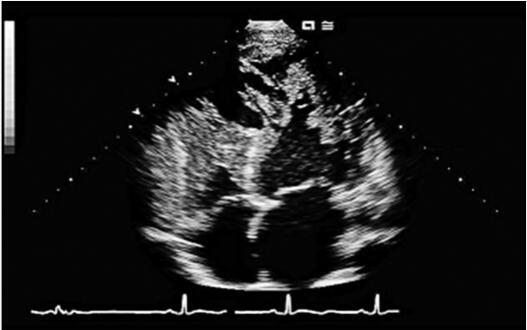

入院后诊治经过:患者收入CCU后,入院查血气分析提示低氧血症。床边胸片提示肺水肿。立即给予吸氧、心电监护,给予强心、利尿、扩血管、解痉平喘等治疗3天后症状缓解,夜间能平卧,两肺干湿啰音消失。入院后复查心脏彩超提示:主动脉根部内径33mm、左房内径45mm、左室舒张末内径59mm、室间隔10mm、左室后壁10mm,LVEF34%,二、三尖瓣中度反流。左室心尖部、前侧壁心内膜面探及多发性突入左室腔内的肌小梁,小梁之间可见深度不同的间隙,病变均累及左室游离壁的中下部,以心尖部及前侧壁为著。室间隔基本正常(图8-4-1)。MRI:左室舒张末期横径58.7mm,侧壁厚度13mm,室间隔厚度10mm,LVEF 37.2%。左室心肌存在增多粗乱肌小梁,肌小梁间可见深陷隐窝,肌小梁间隐窝与左室腔交通(图8-4-2);次日至导管室行冠状动脉造影示:左右冠状动脉均正常。综合入院后多项检查结果我们排除了冠心病、高血压性心脏病、风湿性心脏病以及心包积液等疾病,本病例科内讨论后我们考虑本病系心室肌致密化不全(NVM)引起。患者入院治疗后症状缓解,10天后出院,出院后带药:改善心室重构(培哚普利,4mg每日1次;美托洛尔6.25mg,每日2次);利尿药:氢氯噻嗪25mg,隔日1次;螺内酯20mg,隔日1次;强心药:地高辛0.125mg,每日1次;抗凝药:华法林3mg每日1次。

图8-4-1 心尖四腔观:心尖部及侧壁心内膜如厚海绵状,心尖部肌小梁粗大,小梁间隐窝明显,隐窝的血液与左心室相通